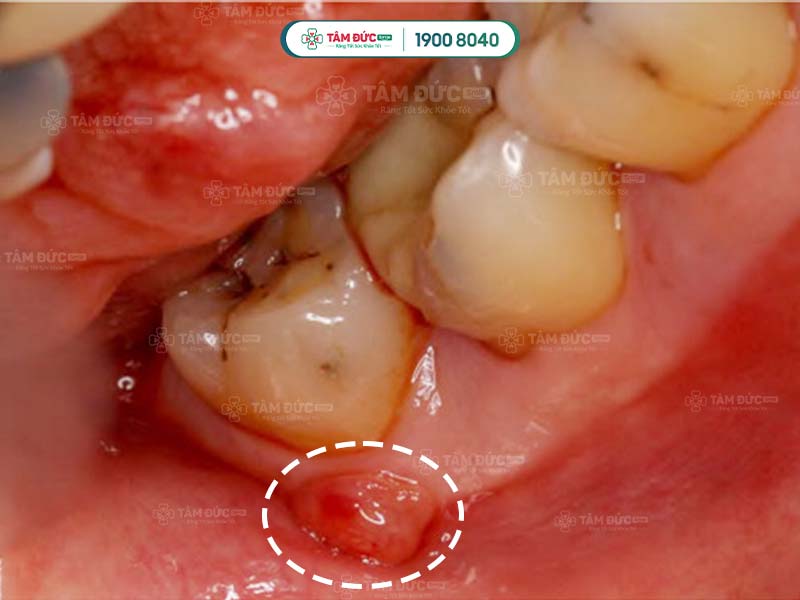

Áp xe răng khôn là thuật ngữ dùng để chỉ răng khôn (răng số 8) bị nhiễm trùng nghiêm trọng, có ổ mủ hình thành ở chân răng. Ở một số trường hợp, ổ mủ xuất hiện trong nướu hoặc cổ răng. Bác sĩ khẳng định, áp xe răng khôn chính là hệ quả của tình trạng viêm nướu, viêm tủy, sâu răng khôn,... không được điều trị kịp thời.

Vùng nướu ở vị trí răng khôn bị sưng đỏ, Quý khách có thể nhìn thấy mủ tích tụ bằng mắt thường.

Răng khôn bị sâu làm tăng nguy cơ hình thành ổ áp xe